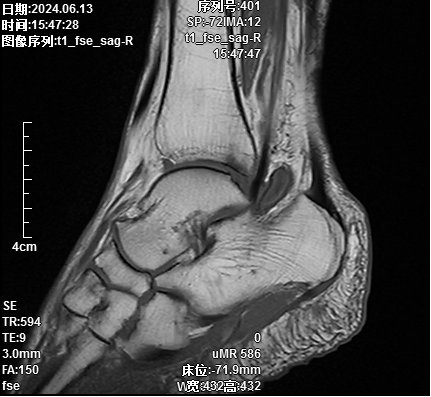

汪某,女,69岁,患者于3+月前发现右足背及右足跟腱处无明显诱因出现包块,行走时疼痛及活动受限,为求解决问题,于是来到我院骨伤科就诊。术前核磁共振提示:1.距骨前外侧、胫骨后侧多发囊肿;2.多发骨质骨髓水肿、小囊变

刘志强医生解释道,踝关节囊肿是一种多发生在肌腱旁的疾病,多因治疗后反复发作。若采取传统开放式手术,切口较大,且对周围软组织干扰严重,导致出现潜在的瘢痕疼痛及瘢痕压迫症状,且影响美观。骨伤科副主任徐驰团队根据患者病情及症状,经讨论后决定为患者行关节镜微创手术,即踝关节镜辅助下右踝关节清理+右足、踝多发囊肿切除术。在医生的细心讲解下,且汪女士既往有腰椎微创手术史,对微创手术的效果满意,于是同意了微创手术治疗。